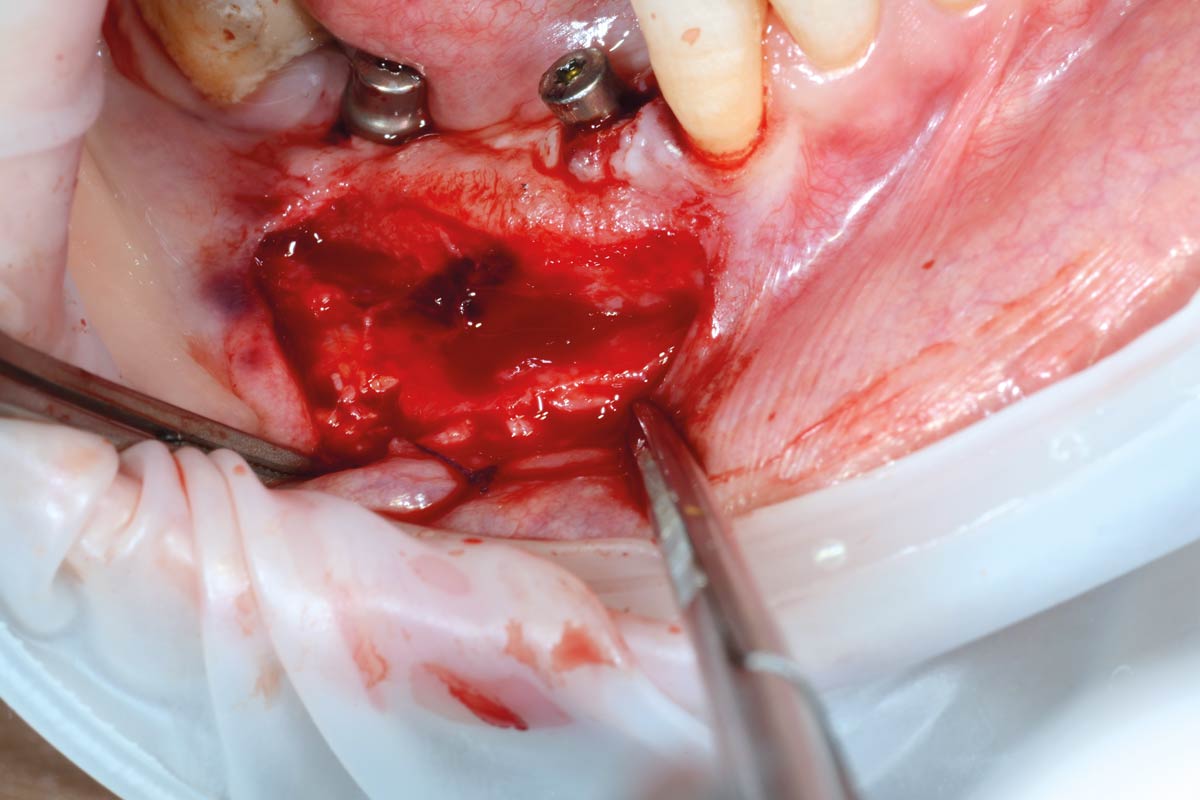

11/29 - Flap opening for removal of permamem®Vertical bone augmentation and broadening of attached gingiva using cerabone®, permamem® and mucoderm® - Dr. R. Naimoli

12/29 - Augmented area in maturation phase exposed under permamem®Vertical bone augmentation and broadening of attached gingiva using cerabone®, permamem® and mucoderm® - Dr. R. Naimoli